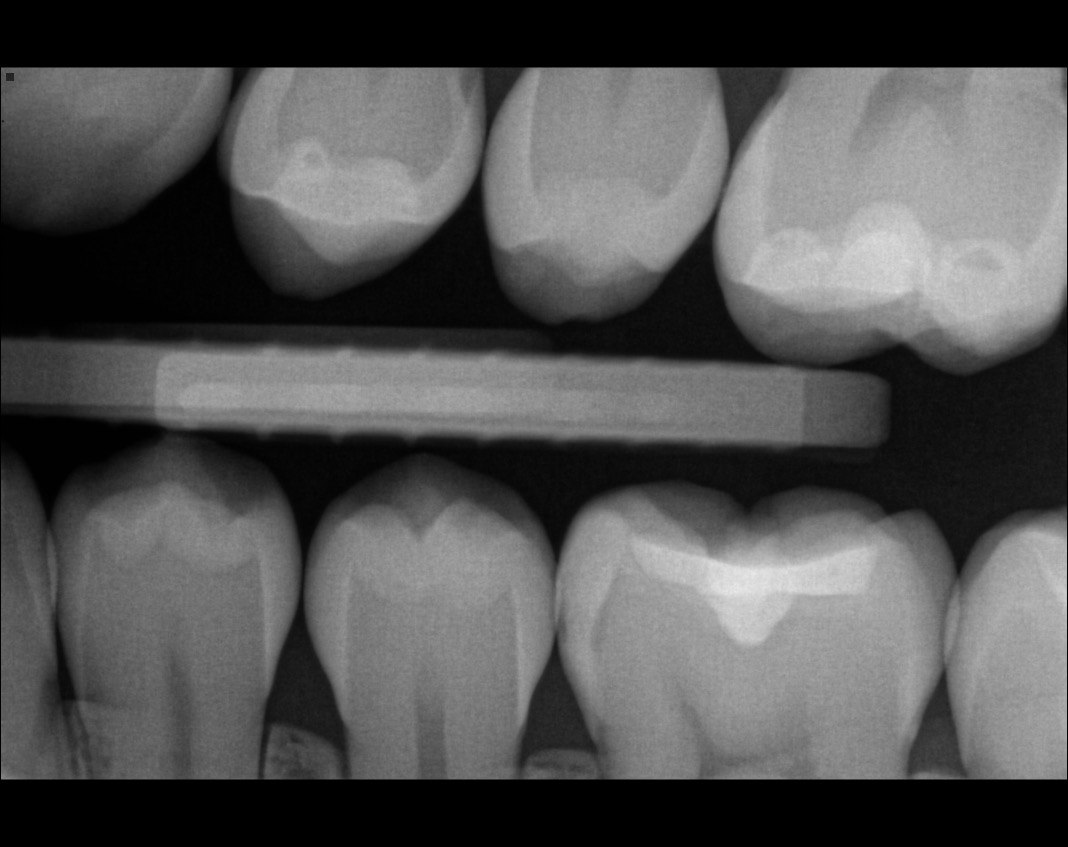

Question 30: What option can be seen on the lower jaw of the following X ray?

Question 31: Which options can be selected for the following X ray?

Question 32: Which surface need restoration?